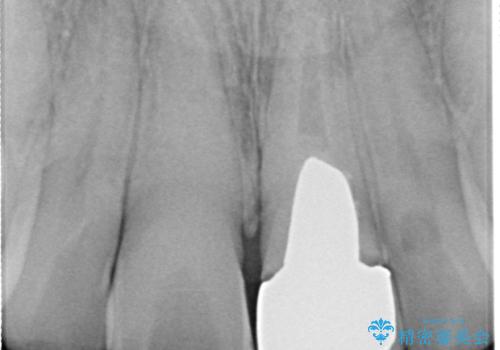

- 幼少期にぶつけてしまった前歯2本の変色を気にして来院された患者様です。

神経は生きているものの歯の色が茶色くなってきており、隣の歯は保険診療で装着したプラスチックのクラウンが徐々に黄ばんできている状態でした。

2本を同時にオールセラミッククラウンにて補綴治療を行うこととしました。